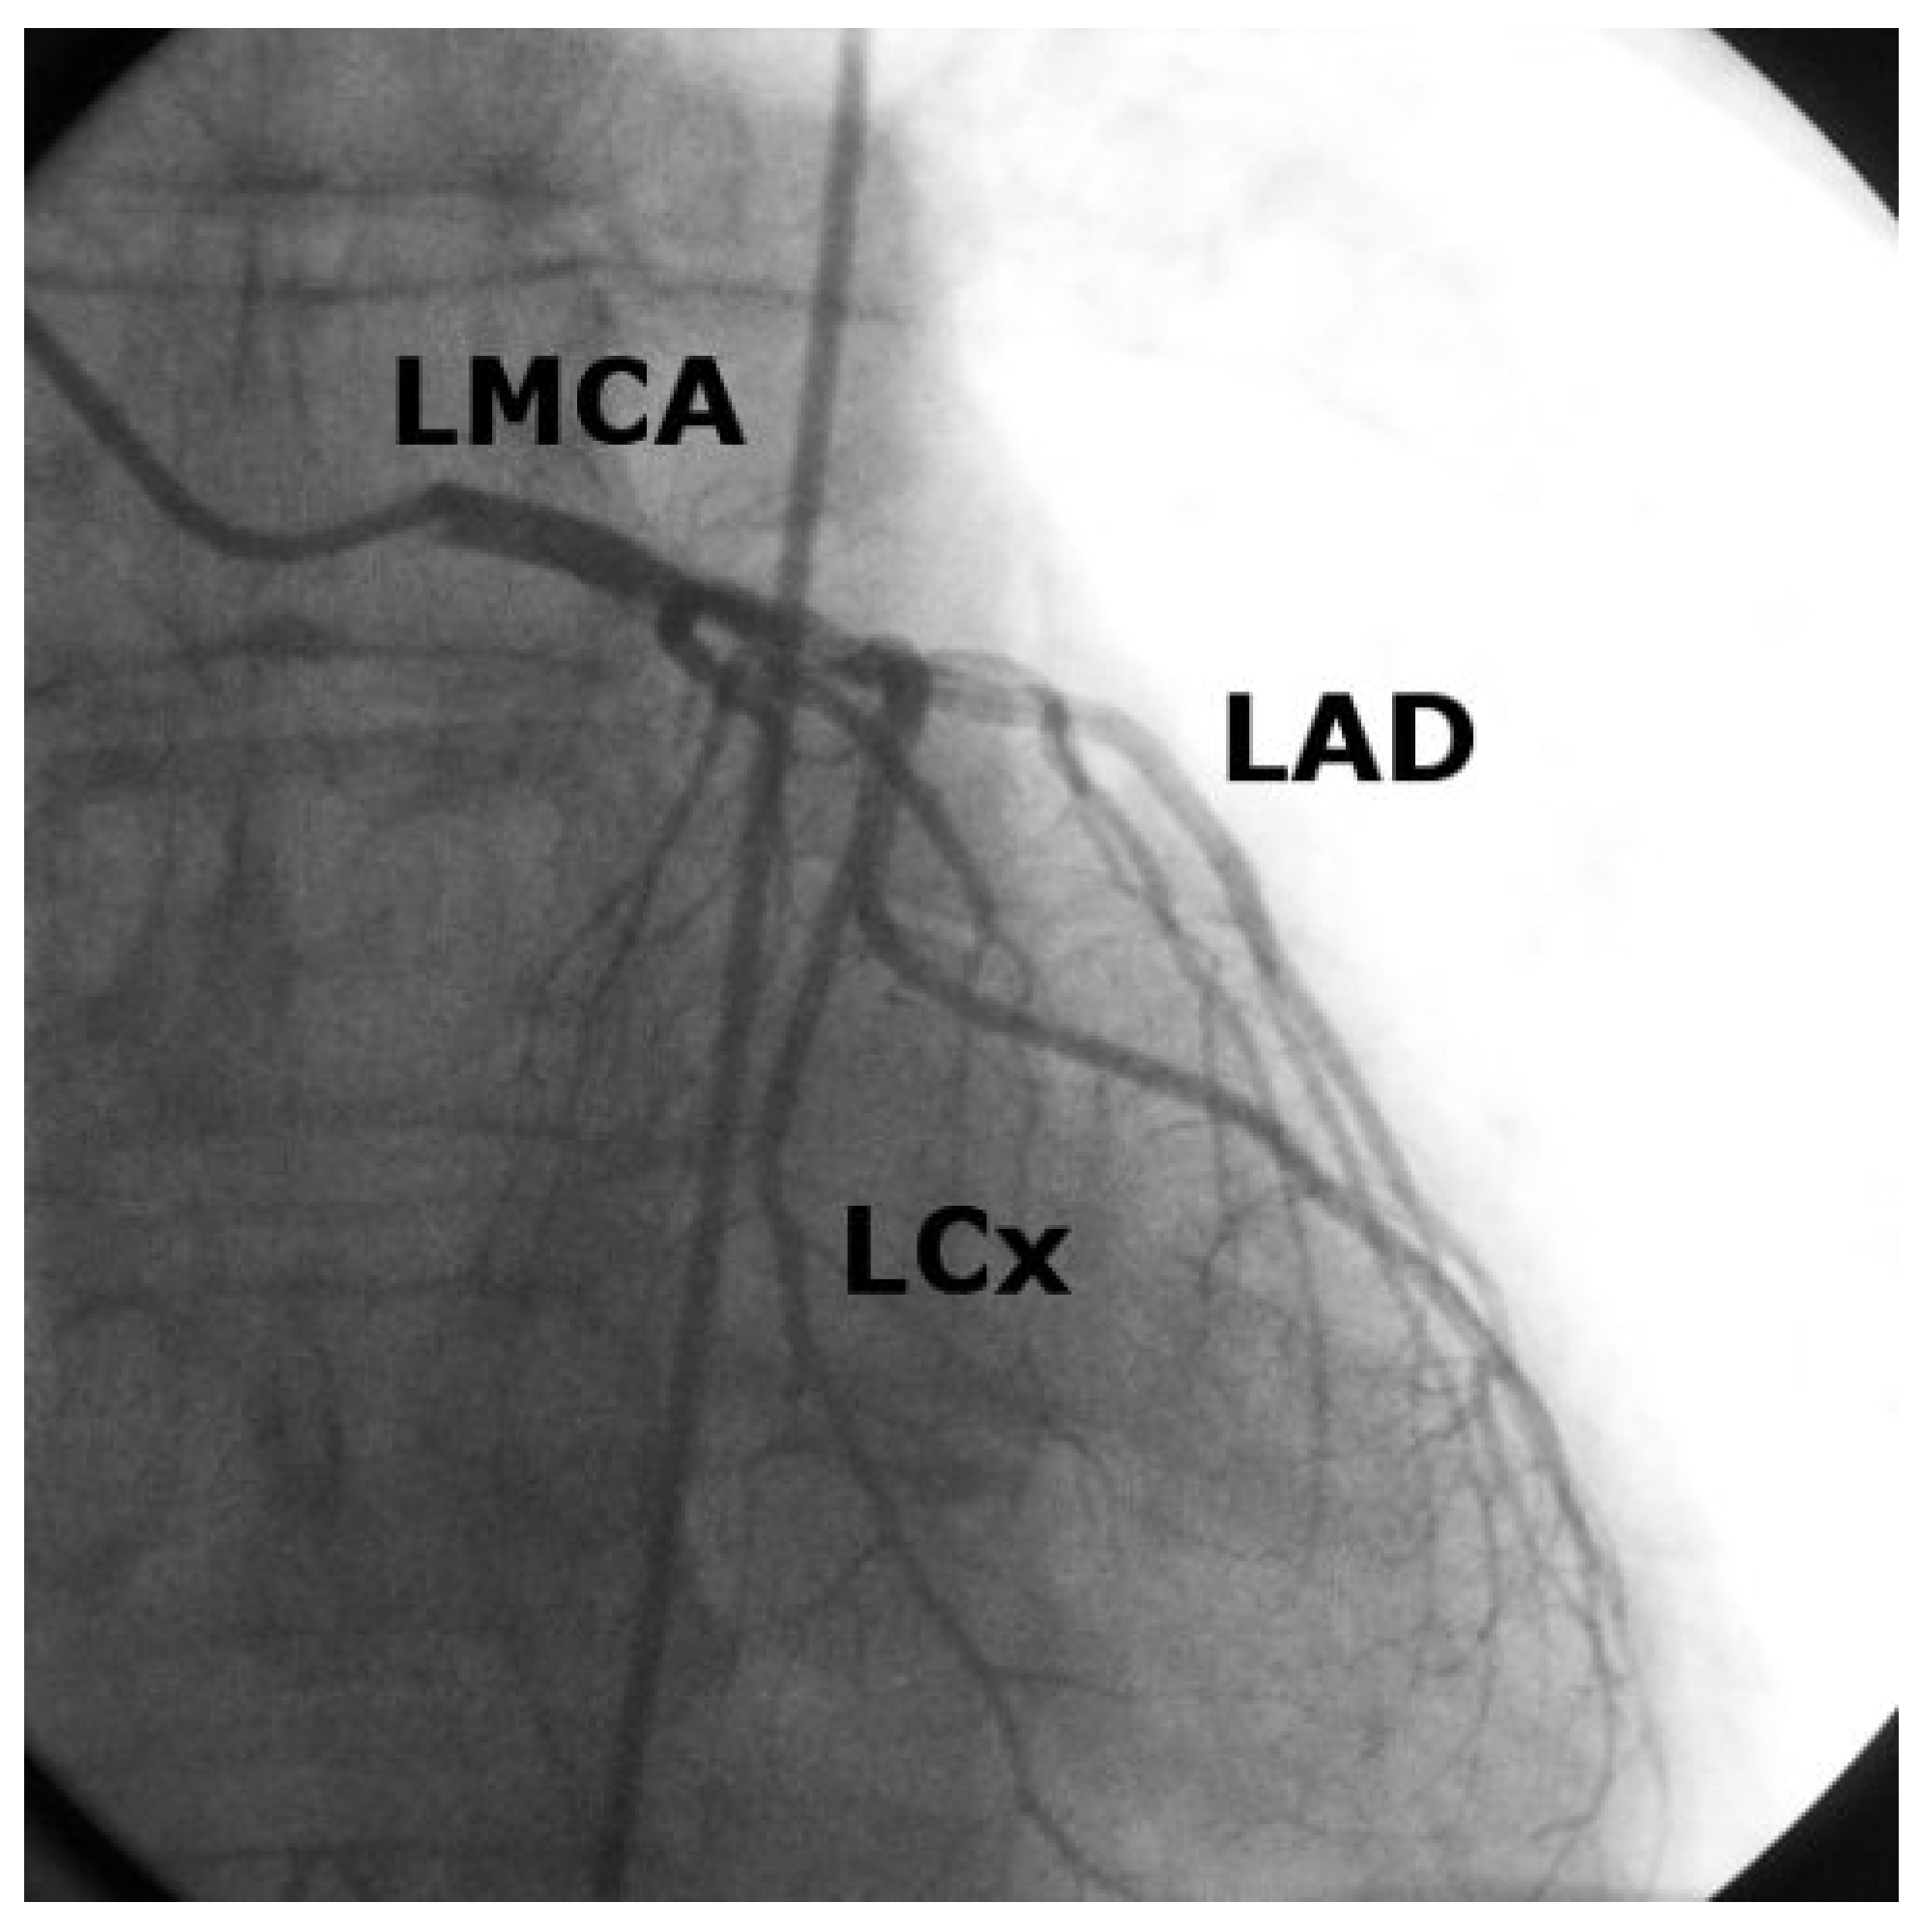

Case2